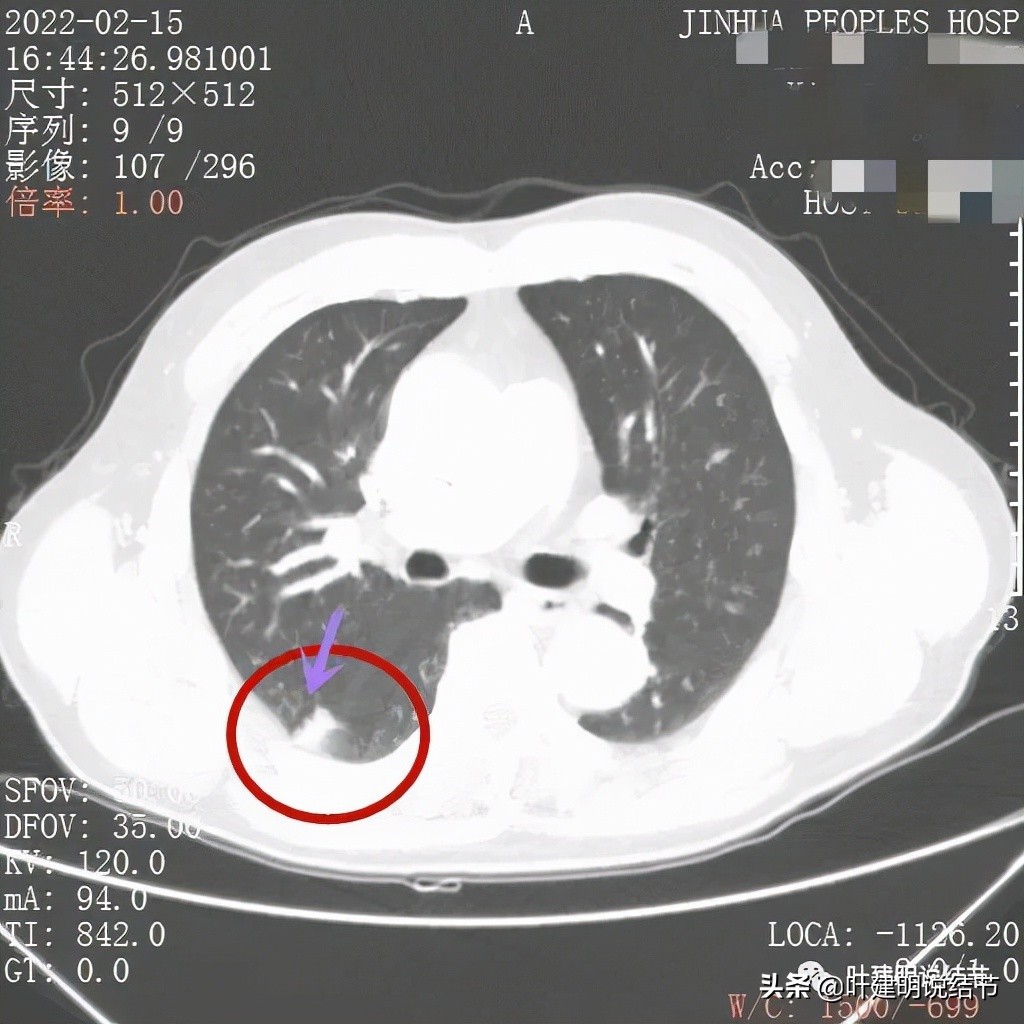

病灶边缘不平,略模糊

边缘似见少许磨玻璃成分(绿色箭头),病灶与胸壁间离的这么近,但有低密度分界(黄色箭头),说明不是普通炎症性,如果炎症会有水肿,间隙一般不清

上图除了间隙以外,病灶有的地方有膨胀性,往外鼓出去一点(砖色箭头)

膨胀性以及与胸壁间隙

上图示病灶边缘毛糙(紫色箭头),以及与胸壁间的间隙存在(黄色箭头)